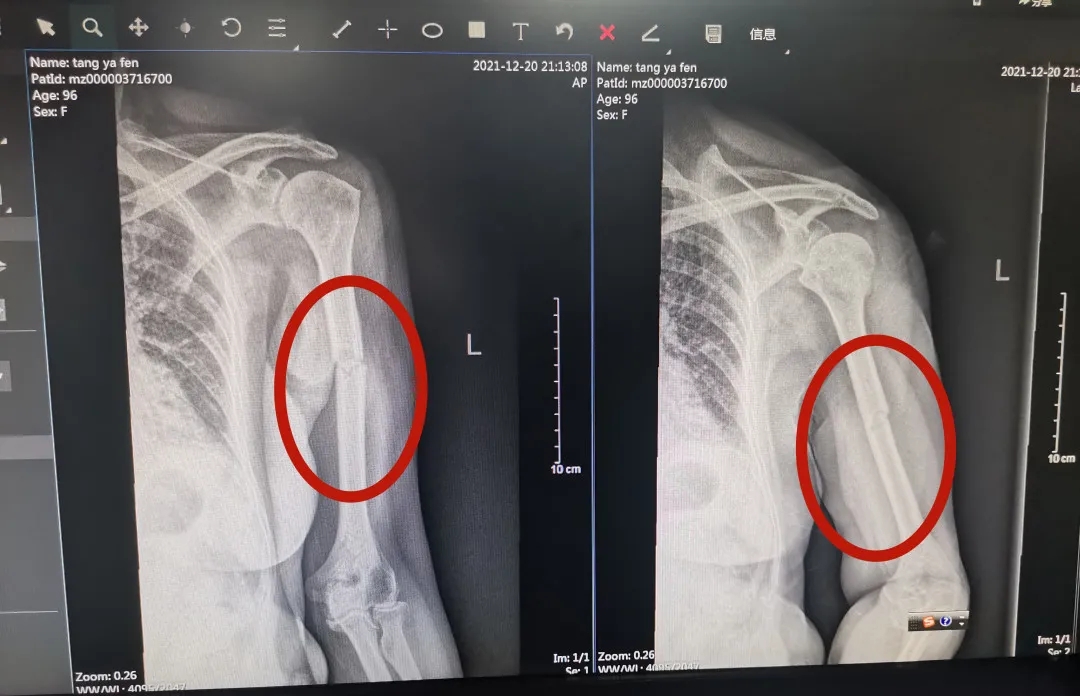

据了解,三年前唐奶奶因不慎摔倒,导致左股骨转子间骨折,遂来到河池市人民医院创伤手外科接受微创PFNA内固定术,术后恢复效果佳,已能正常行走。2021年12月26日,唐奶奶在家又不慎摔倒,出现左上臂疼痛、畸形、不能屈伸活动,剧烈的疼痛使她难以起床,生活无法自理。唐奶奶的子女们回想起上一次手术后的良好效果,于是,他们再次来到河池市人民医院创伤手外科请求帮助。创伤手外科副主任姚泓成得知情况后,仔细查看检查结果,诊断为左肱骨干骨折,考虑到老人已经96岁高龄,再加上患有多年的高血压、冠心病,姚泓成副主任组织医疗团队第一时间展开讨论,最终决定为老人做骨折手术。

唐奶奶本次手术前X线检查结果